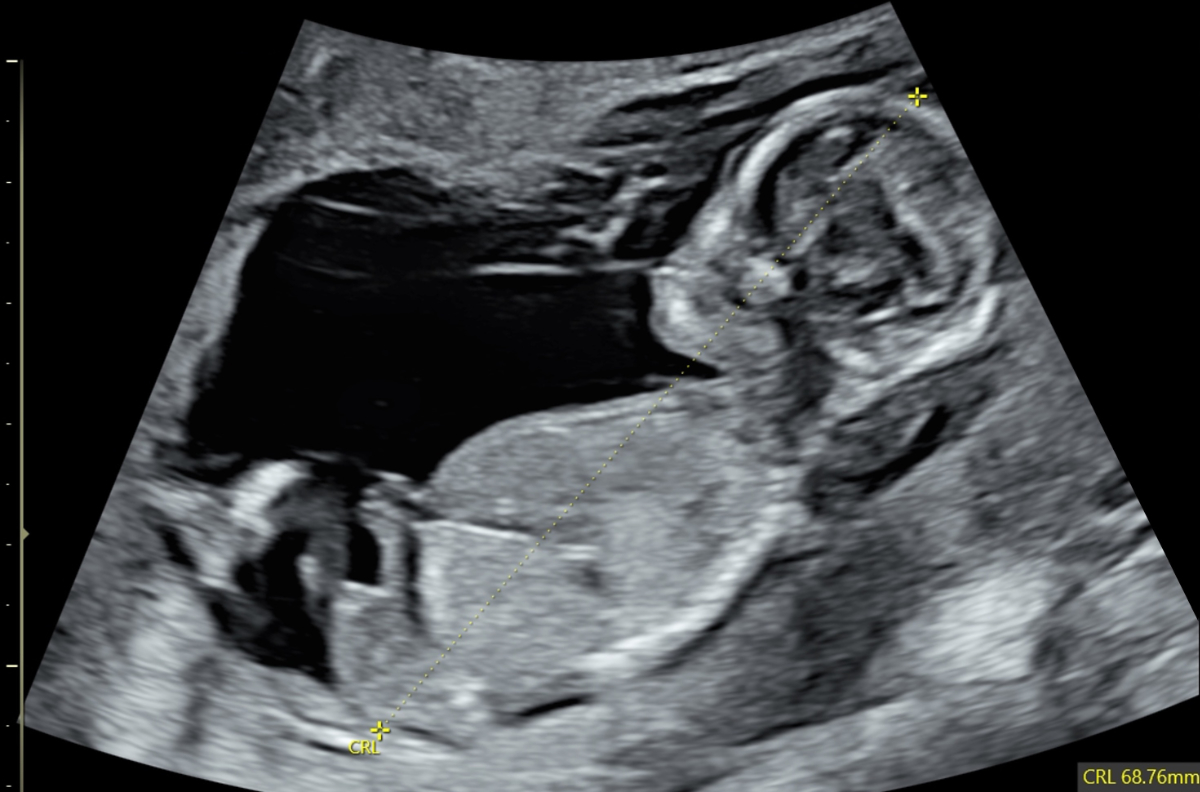

First trimester screening is not limited to detecting trisomies 13/18/21; it is essential for early identification or exclusion of many major structural anomalies (see figures 3–5). According to the current Swiss guidelines [3], combined testing for trisomies should be offered only when no significant malformations have been found and when nuchal translucency is below the 95th centile. Otherwise, diagnostic procedures should be offered.

Figure 5Abnormal profile and missing nose in a 13-week foetus (CRL 68.76 mm). CRL: crown-rump length.